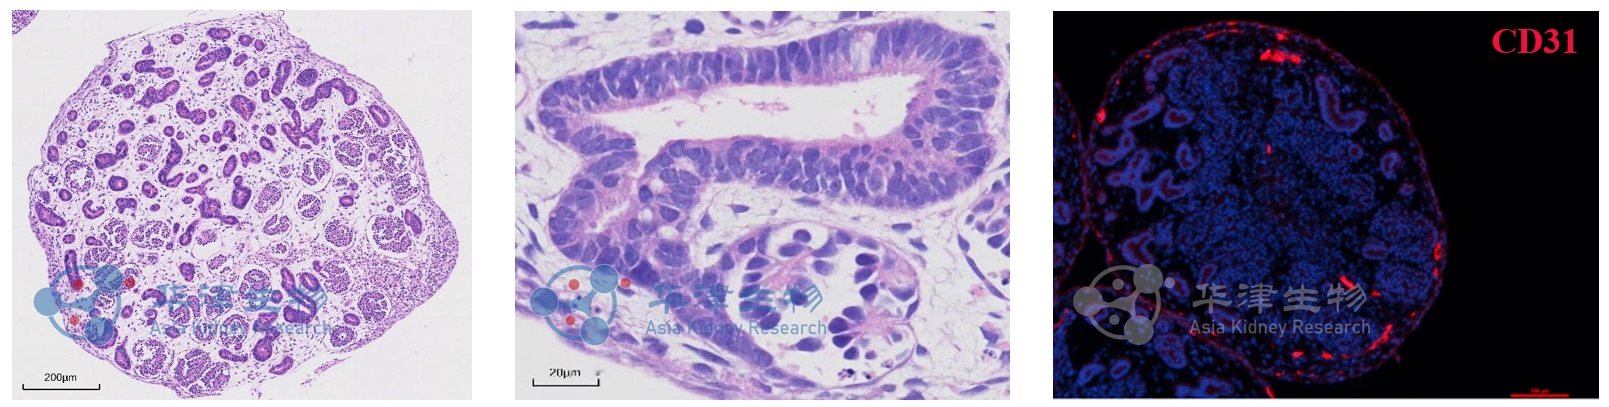

图2. 经病理切片图和荧光染色图鉴定,Kidnioid®技术平台构建的肾脏类器官包含肾小球、肾小管及血管样结构

华津生物肾脏类器官Kidnioid®技术平台基于人多能干细胞(iPSC/ESC),通过模拟肾脏在体发育过程,构建具有肾小球、肾小管、血管样结构等多细胞组分的肾脏类器官。

高度仿生:具备足细胞、近端小管、远端小管等典型结构,电镜显示丰富足突结构。